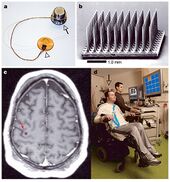

HochbergFig1.jpg

There was not much advancement in neurosurgery until late 19th early 20th century, when electrodes were placed on the brain and superficial tumors were removed.

History of electrodes in the brain: In 1878 Richard Caton discovered that electrical signals transmitted through an animal's brain. In 1950 Dr. Jose Delgado invented the first electrode that was implanted in an animal's brain, using it to make it run and change direction. In 1972 the cochlear implant, a neurological prosthetic that allowed deaf people to hear was marketed for commercial use. In 1998 researcher Philip Kennedy implanted the first Brain Computer Interface (BCI) into a human subject.[16]